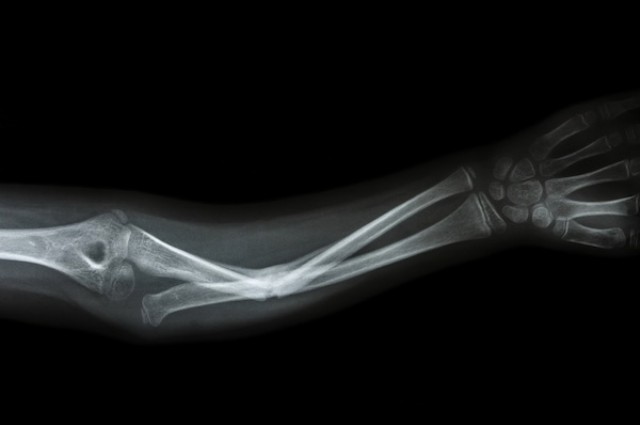

Using proteins secreted by stem cells, researchers may have found a new, less risky way to regenerate bone tissue for people who have suffered major trauma to their limbs. According to findings published in Scientific Reports this week, the technique could one day provide a sustainable source of fresh tissue.